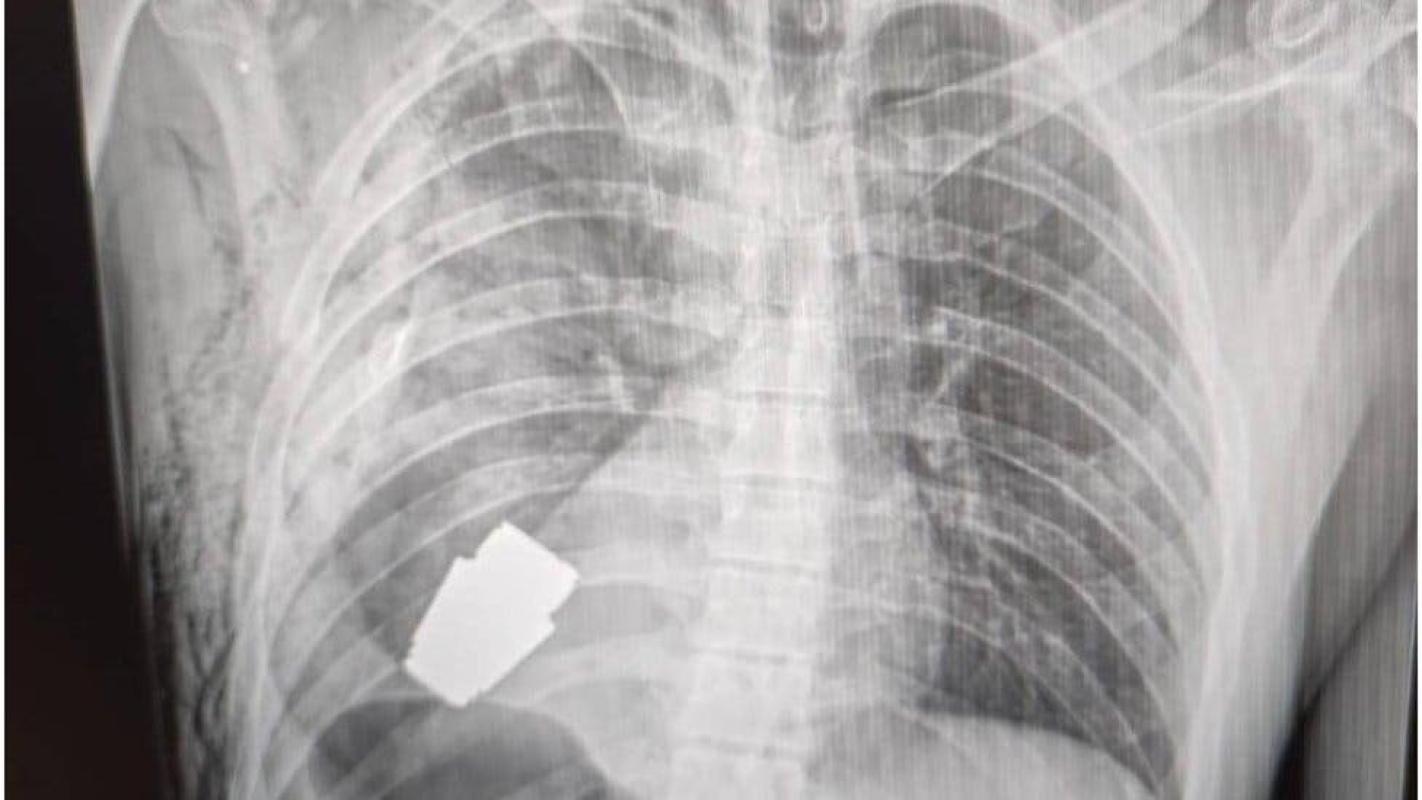

El gobierno ucraniano describió como un "susto afortunado" la terrible experiencia por la que tuvo que pasar un soldado herido, a quien le extrajeron con éxito una granada que se encontraba en su pecho.

El fragmento de la granada de fabricación rusa que quedó alojado en el cuerpo del soldado tenía cuatro centímetros de diámetro y pesaba 275 gramos.